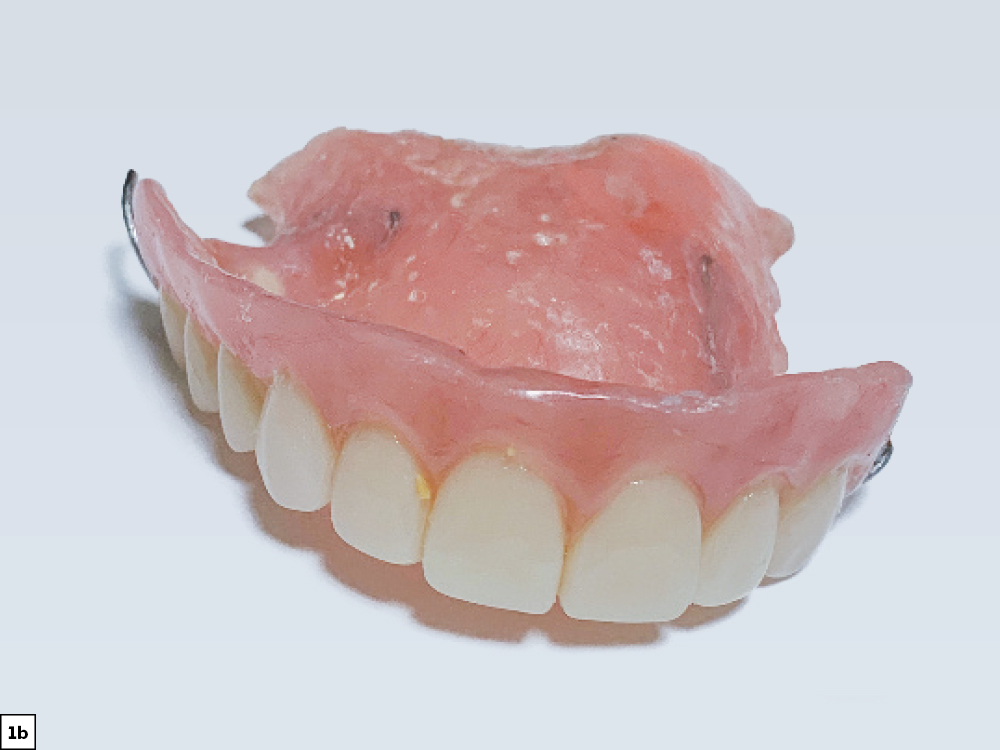

A previous removable partial denture of a patient

Four added implants to support an FP-3 prosthesis

Figures 1a, 1b: At the initial consultation, the patient complained of her removable partial denture, desiring a fixed restoration that looked and felt more like natural teeth and would allow her to eat normally and smile without worrying about her prosthesis becoming loose. Because the patient’s remaining teeth were healthy and a conventional bridge was not an option, the patient agreed to receive four implants to support an FP-3 prosthesis, which would replace the missing teeth as well as the lost hard and soft tissue in the edentulous span.